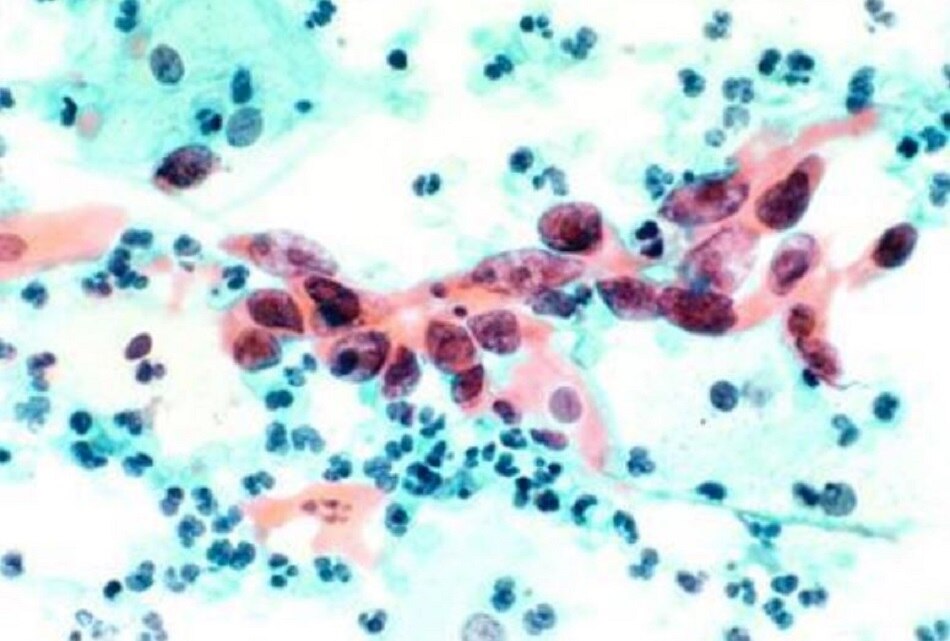

बिना साइड इफेक्ट कैंसर के इलाज में वैज्ञानिकों को मिली सफलता, बढ़ जाएगी मरीजों की उम्र

इजरायल की तेल अवीव यूनिवर्सिटी के वैज्ञानिकों ने कैंसर के इलाज के लिए एक अभूतपूर्व तरीके की खोज की है. वैज्ञानिकों ने कहा है कि DNA में बदलाव करके उन्होंने चूहे में कैंसर सेल्स को खत्म कर दिया. कैंसर विशेषज्ञ प्रोफेसर डैन पीर का कहना है कि उन्हें उम्मीद है कि दो साल में नई तकनीक से इंसानों का इलाज हो सकता है.

टाइम्स ऑफ इजरायल में प्रकाशित रिपोर्ट के मुताबिक, एक्सपर्ट का कहना है कि नई तकनीक का कोई साइड इफेक्ट नहीं है. साथ ही वैज्ञानिकों का यह भी मानना है कि नई तकनीक से जिन कैंसर सेल्स को खत्म किया जाएगा उनके दोबारा एक्टिव होने की संभावना नहीं रहेगी.

Science Advances जर्नल में प्रकाशित रिपोर्ट के मुताबिक, वैज्ञानिकों का कहना है कि नई तकनीक से उन्होंने चूहों में कैंसर वाले सेल्स को खत्म कर दिया और अन्य सेल्स को कोई नुकसान नहीं पहुंचा. CRISPR Cas-9 तकनीक के जरिए वैज्ञानिकों ने डीएनए में बदलाव किया.

स्टडी में सैकड़ों चूहों को शामिल किया गया था जो गंभीर किस्म के कैंसर से जूझ रहे थे. स्टडी में देखा गया कि ट्रीटमेंट पाने वाले चूहों की उम्र अन्य बीमार चूहों के मुकाबले दोगुनी हो गई. प्रोफेसर डैन पीर ने कहा है कि नई तकनीक से कैंसर के मरीजों की उम्र बढ़ सकती है और फिर बीमारी का पूरी तरह इलाज भी हो सकता है. उन्होंने कहा कि तीन बार के ट्रीटमेंट कैंसर सेल्स को पूरी तरह खत्म कर सकता है.